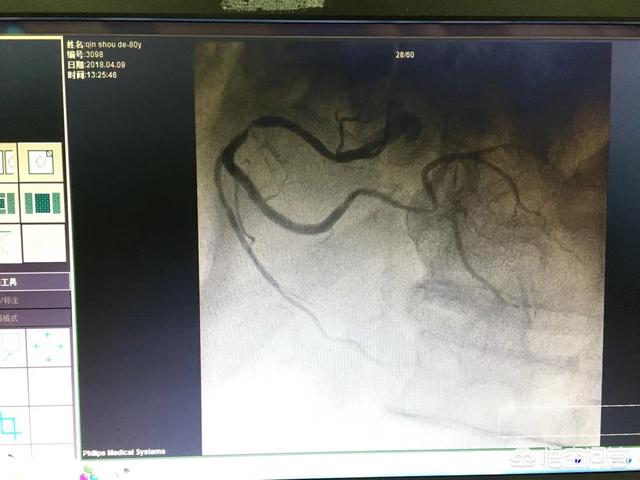

La coronarographie n'est utilisée que comme preuve solide pour confirmer un diagnostic de maladie coronarienne.Il n'a que peu d'importance pour le diagnostic d'autres types de maladies cardiaques.

Le symptôme le plus typique de ce type de patients est une douleur thoracique sourde et oppressante, qui survient le plus souvent après une activité physique et peut irradier vers l'épaule gauche, le bras gauche, la mâchoire supérieure, les dents, etc. Une échographie cardiaque, un électrocardiogramme, un scanner coronaire, une angiographie coronaire doivent être réalisés à des fins d'examen.